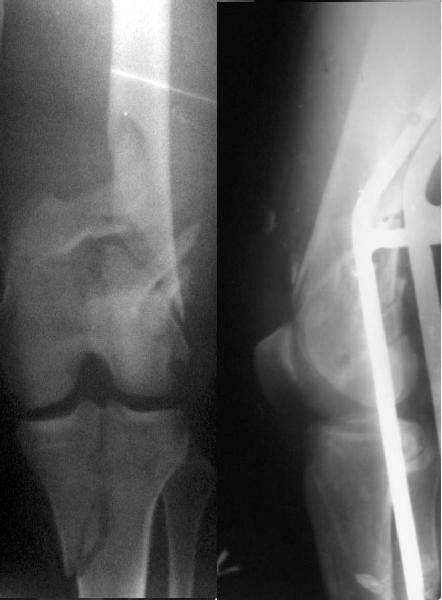

This is what we have done... As generally true for LISS look at the bone not the hardware.

There are two more srews above. The one not completely in got damaged head.

Zsolt